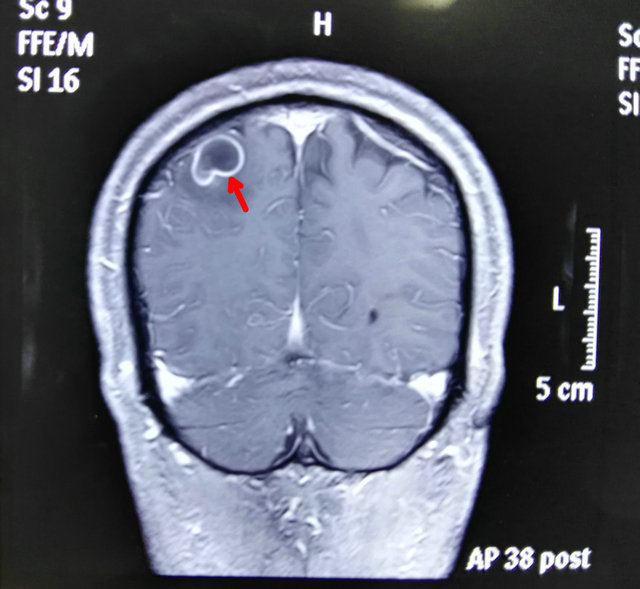

患者李先生今年35岁,一个月前发现左手拿东西不稳了,并且还伴有麻木症状,在多次求医无果后来到郑州大学五附院神经外科一病区。医生经过仔细检查后给李先生诊断为右侧顶叶(中央后回)占位性病变(图1、2)。该病变所处部位十分重要,周围神经、血管复杂,且病变较小,如果术中定位不准,可能会增加副损伤,若稍有不慎可能导致患者偏瘫。

图2